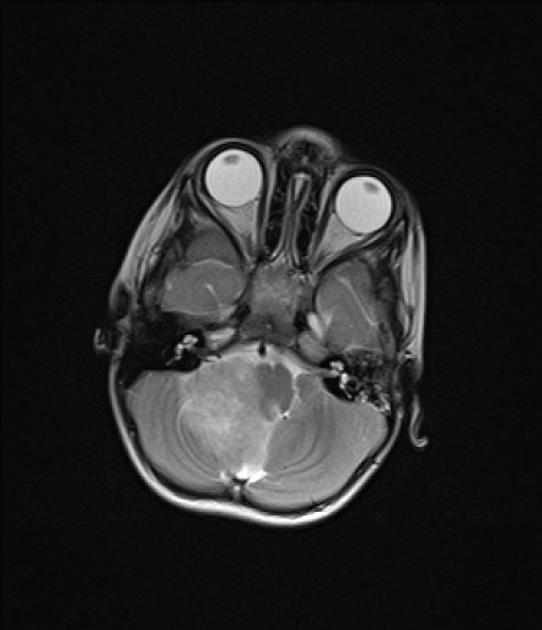

- MRI: The gold standard for diagnosing ependymomas. These tumors typically appear as well-demarcated, heterogeneous masses that enhance with contrast.

- MRI: Ependymomas 진단의 금본위. 이러한 종양은 일반적으로 경계가 명확하고 조영제로 강화되는 이질적인 덩어리로 나타납니다.

- T1: Isointense or hypointense relative to brain or spinal cord.

- T2: Hyperintense with possible cystic changes.

- Contrast Enhancement: Typically shows enhancement, often heterogeneous.

- T1: 뇌 또는 척수에 비해 등신호 또는 저신호.

- T2: 낭성 변화를 동반한 고신호.

- 조영 증강: 일반적으로 이질적인 증강을 보입니다.